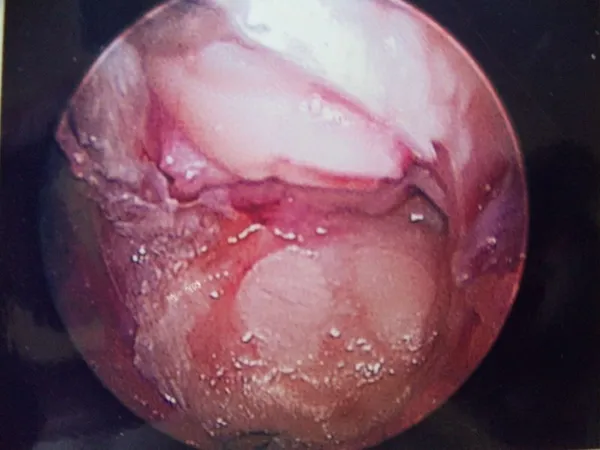

Intraop Pics of Synchondrosis sesamoid fracture

The fracture can be seen. Due to continued pain, a sesamoidectomy was performed. The bone is unhealthy and was removed.